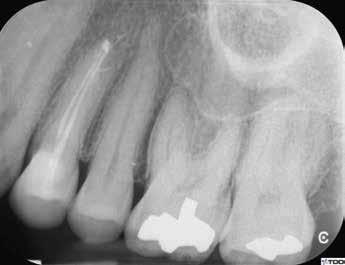

1. a–g. ábrák: A direkt pulpasapkázás lépései. Kiindulási bitewing-felvétel: A meglévő restaurátum közel helyezkedett el a pulpakamrához (a). Kiindulási periapicalis felvétel: Nincs periapicalis elváltozás fennállására utaló jel (b). A pulpaexpozíció (c). A vérzéscsillapítás céljából 20 másodpercen keresztül steril vattagombóccal történő kompressziót követően látható pulpaseb (d). A pulpasapkázás céljából behelyezett anyag, a széli részek tisztázása előtt készült felvétel (e). A röntgenárnyékot nem adó ideiglenes tömés behelyezése után készült felvétel (f). Az első ülés végén a röntgenárnyékot nem adó ideiglenes töméssel ellátott fogról készített röntgenfelvétel (g).

2. ábra: A hat hónapos kontroll alkalmával készített röntgenfelvételen vastag dentinhíd látható a pulpasapkázó anyag alatt.

3. ábra: A hároméves kontroll alkalmával készített röntgenfelvételen megfigyelhető a restaurátum pontos illeszkedése.